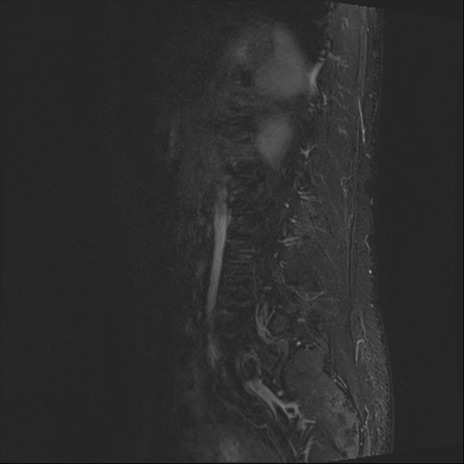

【整形】TIPS症例4 腰椎MRI STIR(矢状断像)

腰椎MRI

T2WI(矢状断像)